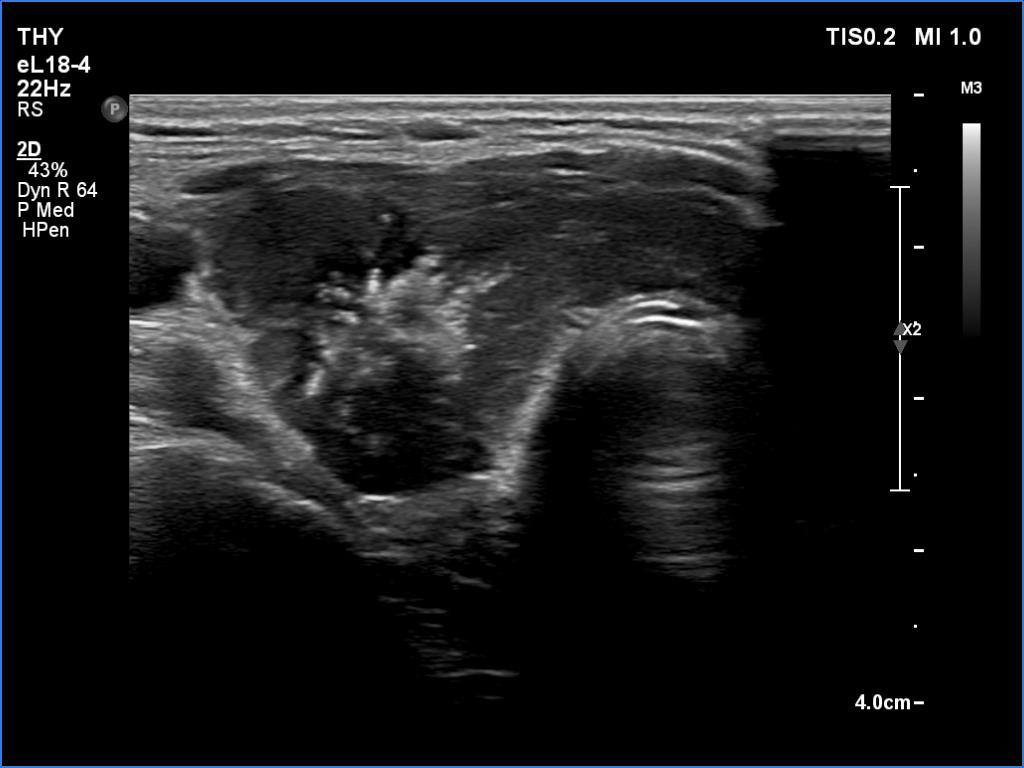

Ultrasonography. The thyroid was hypoechoic. The right lobe had a heterogeneous, dominantly minimally/moderately hypoechoic nodule in the ventrolateral part which had irregular borders and both perinodular and intranodular vascularity. There was another, hyperechoic star-like lesion in the central part of the right lobe. This lesion presented microcalcifications and was avascular. The left lobe was homogeneously hypoechoic.